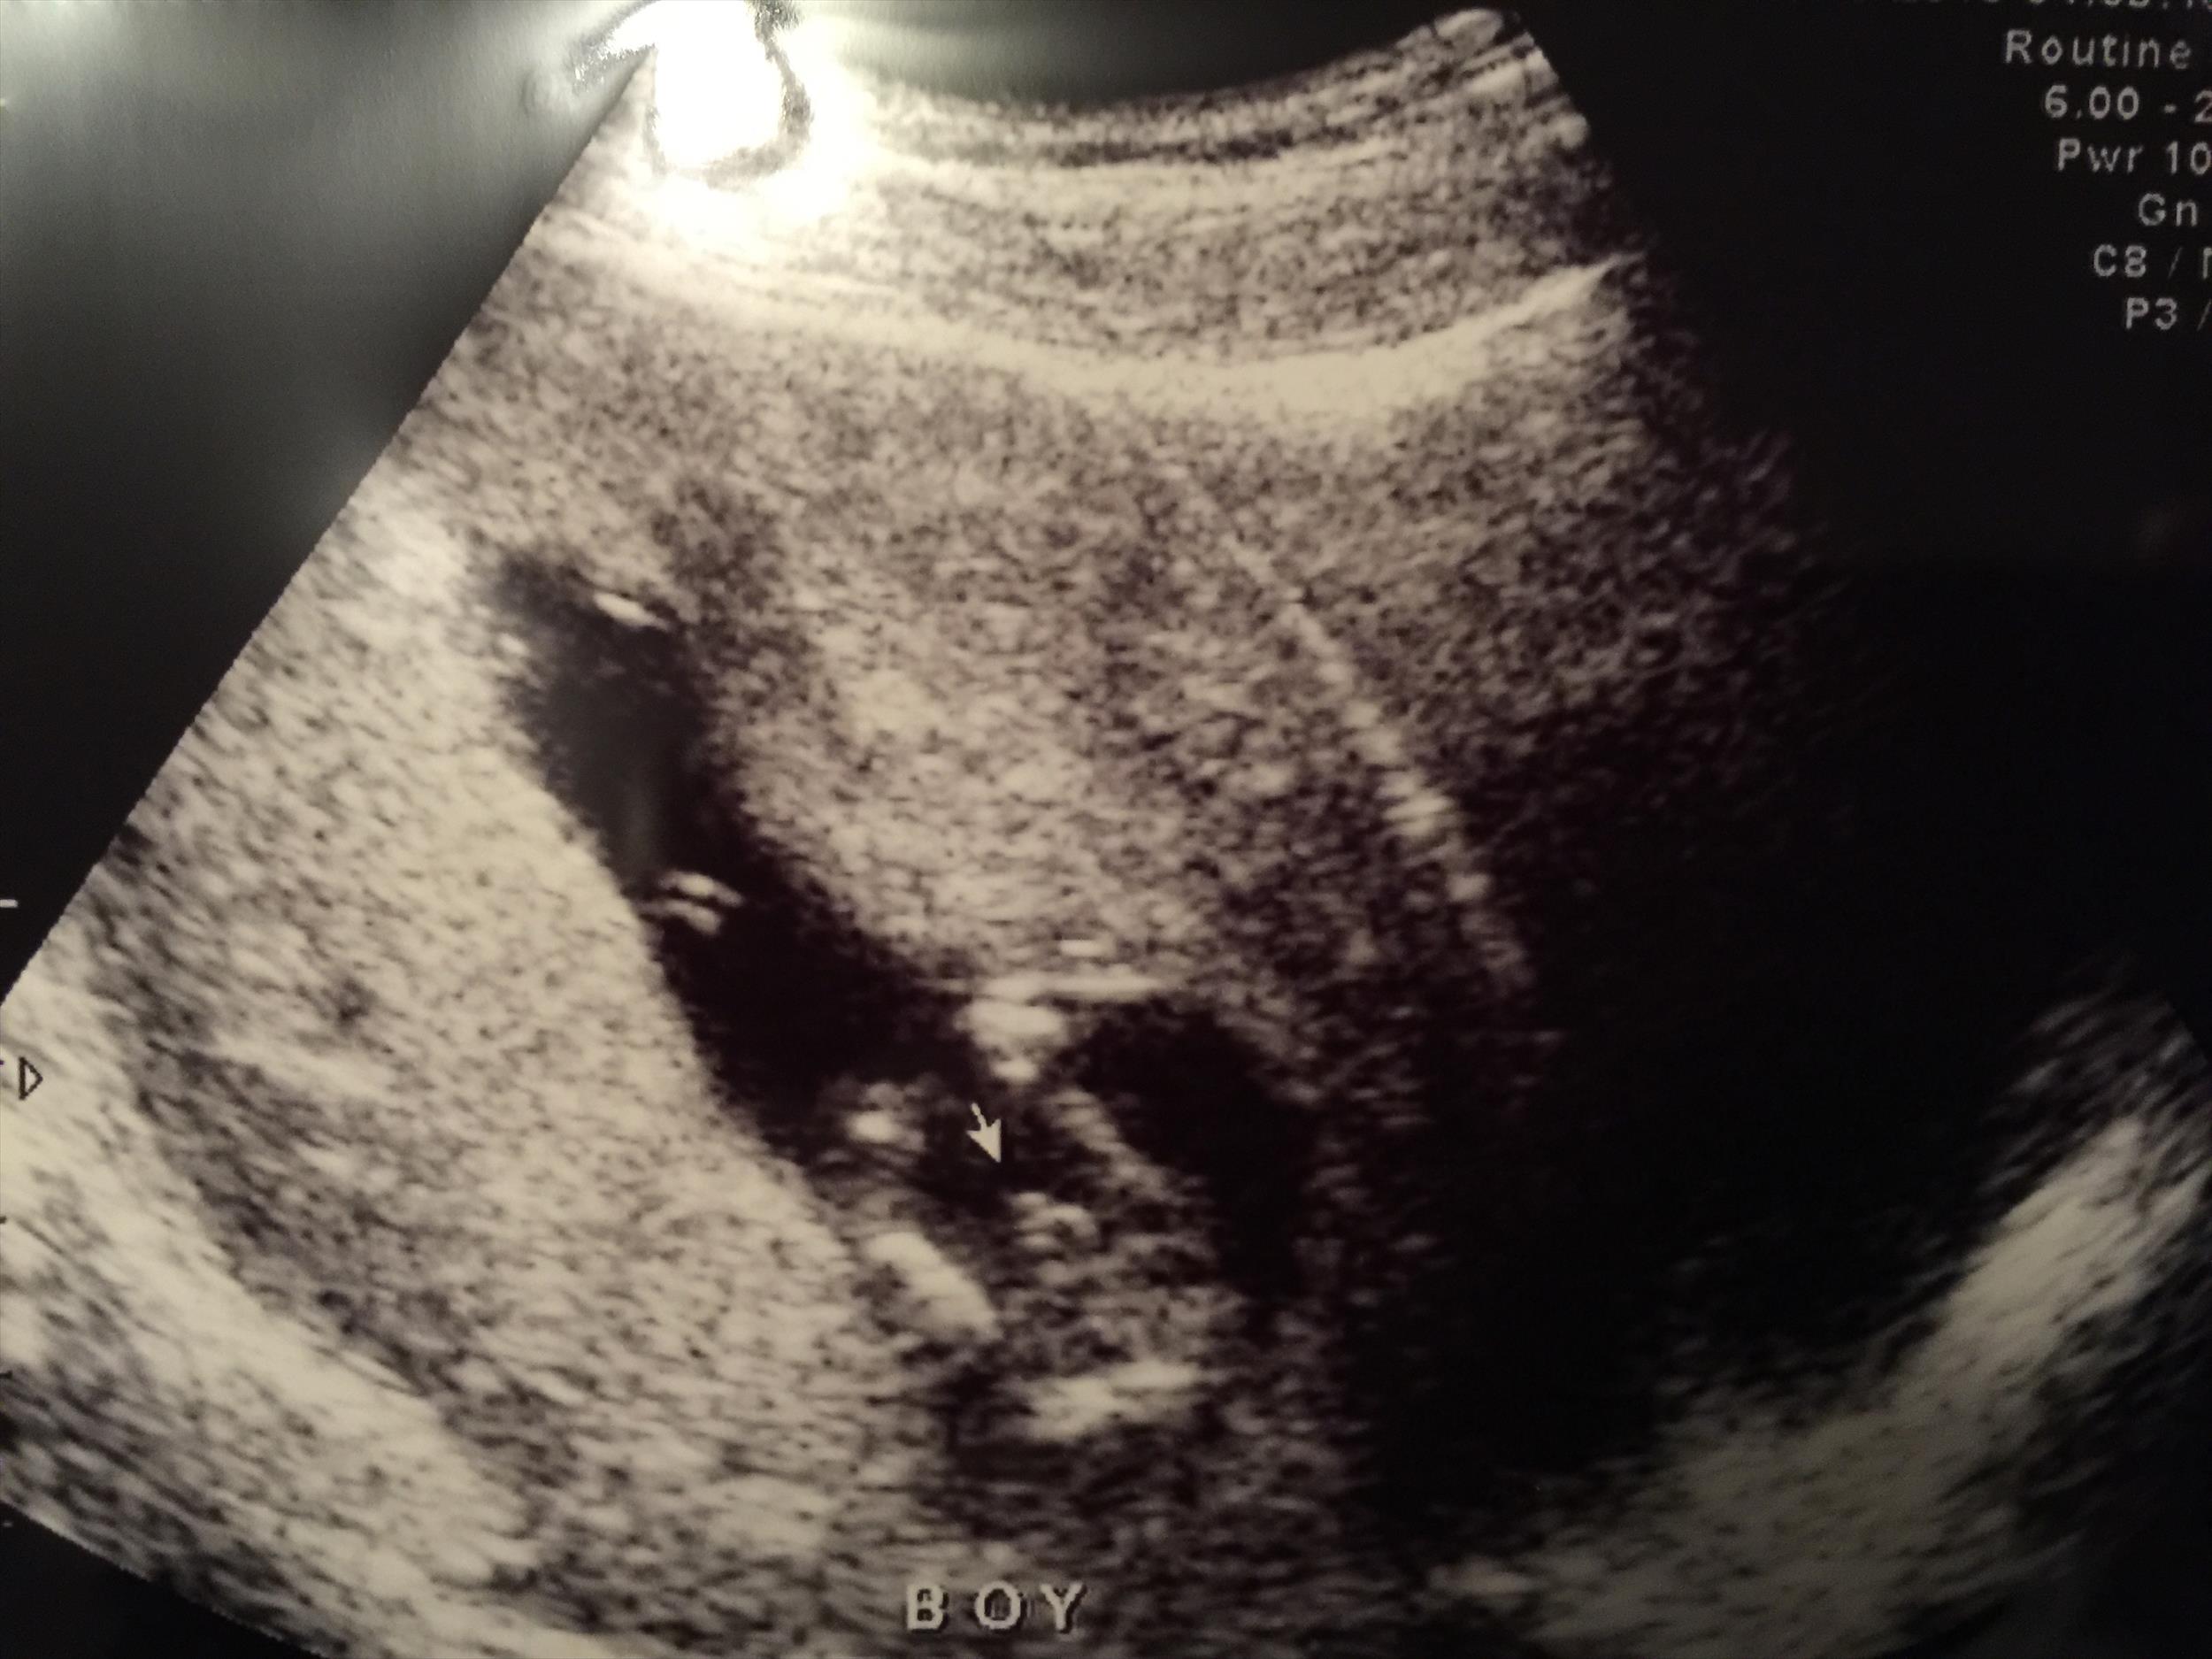

Just got a gender ultrasound at 13wk5d. Sonographer says "boy" but I wanted to make sure she didn't make a mistake. Please let me know if it's pretty obvious in these pictures. Thanks so much :)